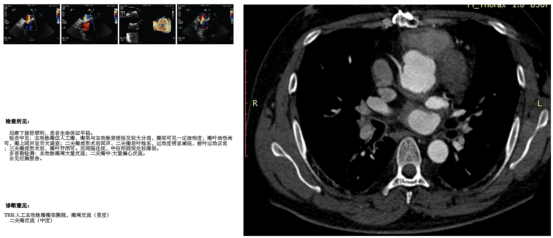

白塞病是一种罕见的全身性血管炎性疾病,可累及多个系统器官,吕先生除了典型的白塞病表现外,还出现了瓣膜术后瓣架撕脱、大量瓣周漏合并主动脉假性动脉瘤的罕见并发症(图1)。由于接受过两次心脏手术,心脏粘连严重,主动脉根部结构复杂。“要缓解当前病情,常规手术方式已经无法解决。”这是摆在肖正华面前的第一个难题。

图 1A 术前经食道超声心动图,B 增强CT